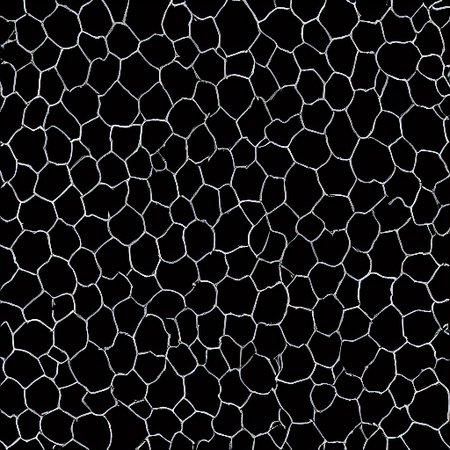

This is a specialized LoRA designed to generate binary segmentation masks for corneal endothelial cells. It produces high-contrast, strictly monochrome (black and white) images representing cell boundaries and structures.

Output: Binary Masks (Black background/White cells or vice versa).

Dataset: 50 manually annotated masks of corneal endothelial photomicrographs.